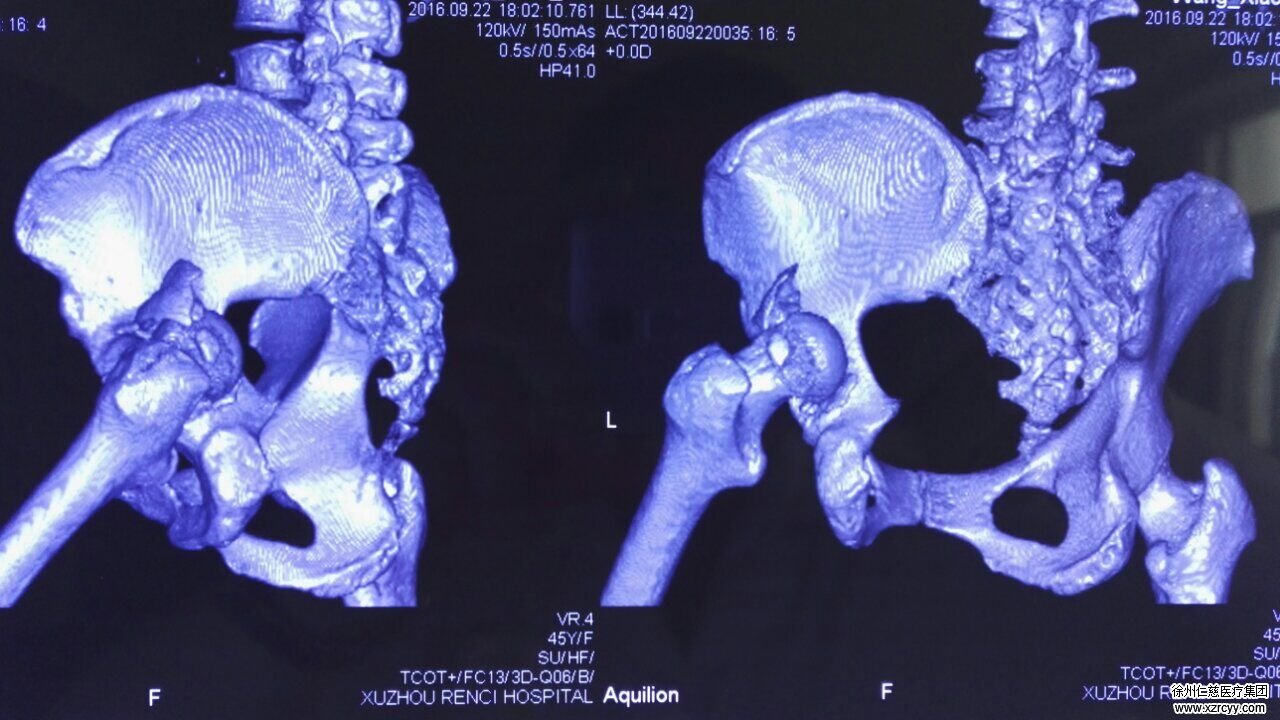

术前CT三维成像

为了渐少病人痛苦,在和病人及家属沟通后,必威官方首页官网betway骨科专家组商议后决定通过术前CT三维成像,1:1复原3D打印髋骨及骨折模型,清晰地显示出患者骨折部位及各血管、神经的解剖位置,辅助完成手术。